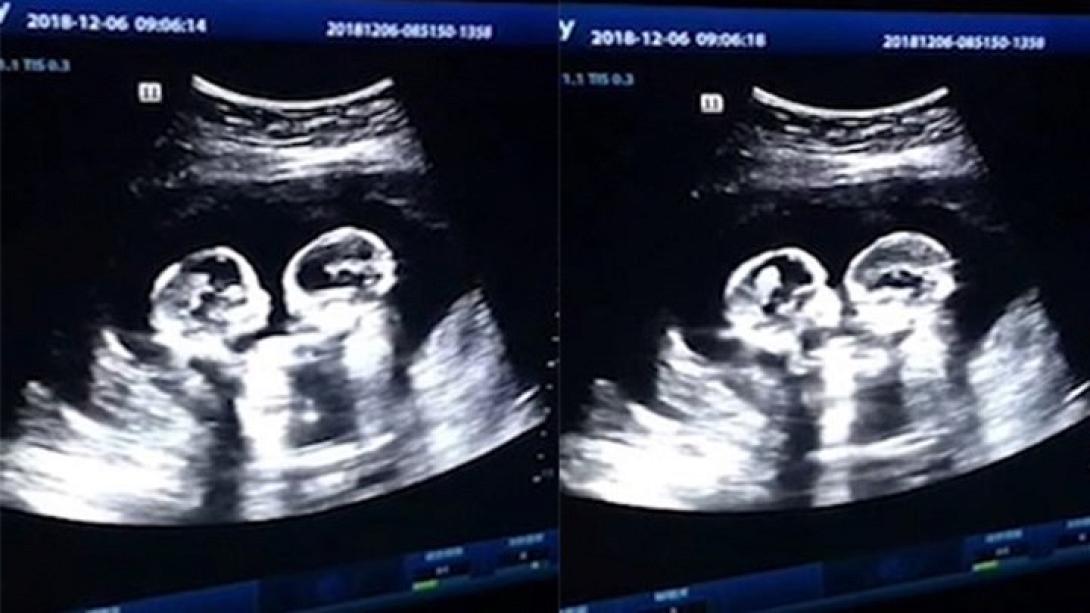

Ομοζυγωτικά δίδυμα καβγαδίζουν μέσα στην κοιλιά της μαμάς τους, σύμφωνα με βίντεο που δημοσιοποιήθηκε και έγινε viral.

Τα δίδυμα κοριτσάκια, που οι γονείς τους αποκαλούν πλέον χαριτωμένα "κεράσι" και "φράουλα" μοιράζονται τον ίδιο σάκο και τον πλακούντα, σε μία σπάνια περίπτωση διδύμων που είναι 1 στις 60.000 κυήσεις.

Τα κοριτσάκια πλακώνονται στο ξύλο, ανταλλάσσοντας κλωτσιές και σφαλιάρες ενώ η μητέρα τους, που διανύει τον τέταρτο μήνα εγκυμοσύνης, υποβάλλεται σε υπερηχογράφημα.